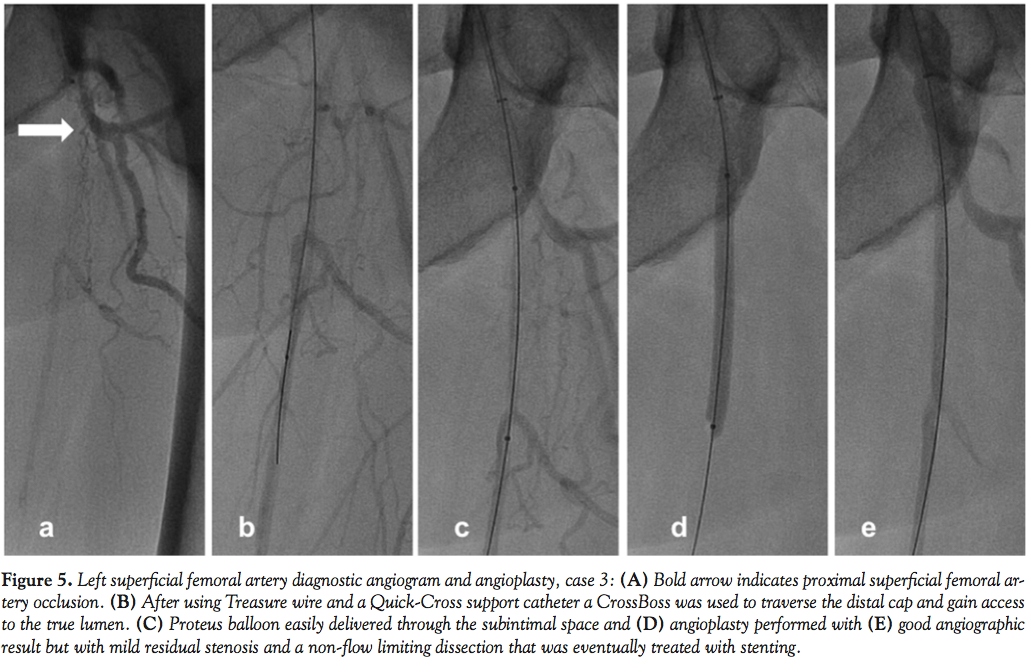

Case 3. A 55-year-old man with hypertension and coronaryartery disease with severe long-standing and life-style limiting bilateral claudication was referred for diagnostic angiography and intervention, and was found to have left SFA occlusion with distal reconstitution in the mid SFA and triple-vessel infrapopliteal runoff (Figure 5A). We again crossed the proximal cap of the SFA with a Treasure wire (Terumo Medical) and a Quick-Cross support catheter (Spectranetics) and used a CrossBoss™ (BridgePoint Medical) to traverse the distal cap and gain access to the true lumen (Figure 5B). Following debulking of the lesion with laser atherectomy (2.0 Turbo Elite®, Spectranetics), the lesion was predilated with a 5.0 x 60 mm Proteus balloon (Figures 5C-5E). Again, the evacuated balloon was unfolded and debris stained with hematoxylin-eosin on a filter (Figure 3C). Following predilation, the residual lesion with a non-flow limiting dissection was treated with a 6.0 x 60 mm nitinol self-expanding stent. Another overlapping 6.0 x 100 mm nitinol stent was placed more proximally. The stented segments were postdilated to achieve an excellent angiographic result with no evidence of distal embolism.